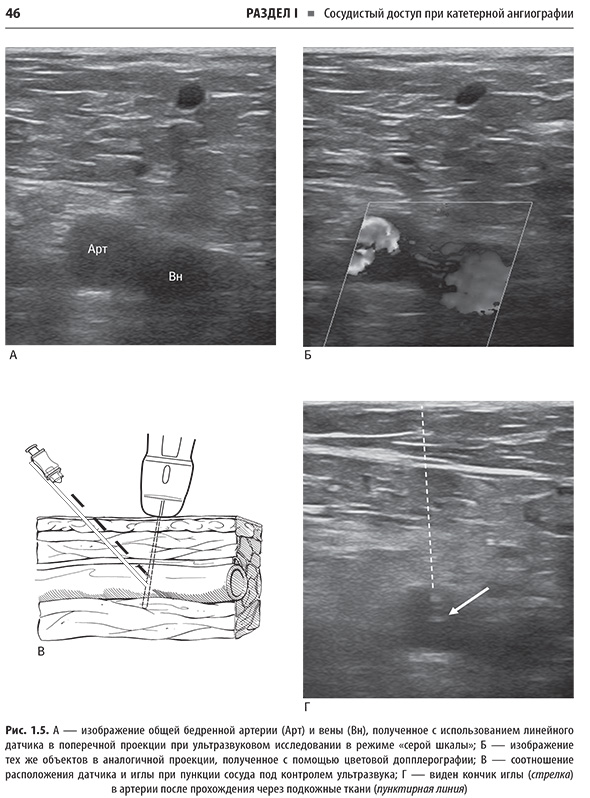

Справочник охватывает все ключевые аспекты, необходимые для успешной практики: показания, противопоказания, подготовку, технику выполнения, ведение пациентов после процедуры, а также профилактику и лечение возможных осложнений. В нем уделено особое внимание протоколам и оборудованию, что позволяет уверенно выполнять сложные манипуляции. Дана информация о сестринском деле, лекарственных препаратах и дозировках, что поможет обеспечить безопасность и комфорт пациентов. Простые линейные рисунки иллюстрируют анатомию и ход процедур, облегчая понимание сложных тем. Представлены сведения о катетерной ангиографии, трансартериальных и трансвенозных процедурах, а также о ведении пациентов во время процедуры.

Примеры страниц из книги "Справочник по интервенционным радиологическим процедурам" - К. Кандарпы, Л. Мачан, Дж.Д. Дюрам